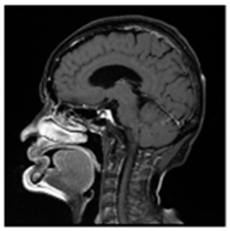

| Original Medical Images | |||||||

| Pair 1 | Pair 2 | Pair 3 | Pair 4 | ||||

![]() (1-9) PSNR = 44.14 | ![]() (1-10) PSNR = 41.90 | ![]() (1-11) PSNR = 40.09 | ![]() (1-12) PSNR = 41.41 | ![]() (1-13) PSNR = 42.24 | ![]() (1-14) PSNR = 40.35 | ![]() (1-15) PSNR = 40.79 | ![]() (1-16) PSNR = 40.84 |

| Shadow Images Produced by Using LSBs | |||||||

![]() (1-17) PSNR = 26.35 | ![]() (1-18) PSNR = 25.49 | ![]() (1-19) PSNR = 23.57 | ![]() (1-20) PSNR = 24.19 | ![]() (1-21) PSNR = 24.79 | ![]() (1-22) PSNR = 24.23 | ![]() (1-23) PSNR = 23.26 | ![]() (1-24) PSNR = 24.42 |

| Shadow Images Produced by Using Middle Bits | |||||||

![]() (1-25) PSNR = 18.97 | ![]() (1-26) PSNR = 19.95 | ![]() (1-27) PSNR = 14.10 | ![]() (1-28) PSNR = 13.84 | ![]() (1-29) PSNR = 16.66 | ![]() (1-30) PSNR = 13.23 | ![]() (1-31) PSNR = 13.38 | ![]() (1-32) PSNR = 14.75 |

| Shadow Images Produced by Using MSBs | |||||||